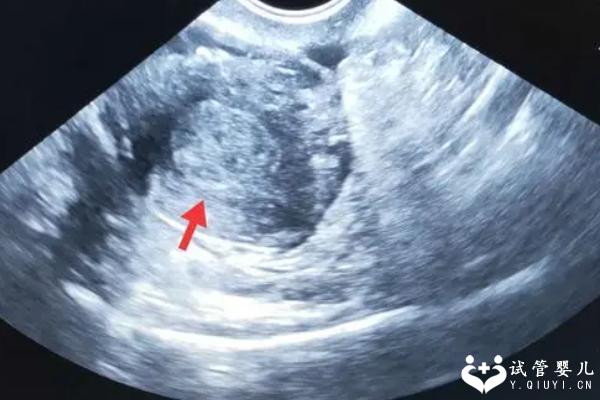

流产是指胎儿未经分娩而自然终止妊娠的过程,也是指胎儿死亡及自然排出助孕的过程,它是一种常见的妇科疾病。流产后,女性病患的自己体内膜可能会出现回声不均匀的情况,因此需要引起重视,并给予适当的治疗。

原因有很多。首先流产可能会导致子宫壁的肌肉痉挛,导致自己体内膜回声不均匀。其次流产后,自己体内膜可能会出现细胞死亡或分泌物增多,从而导致自己体内膜回声不均匀。此外大量抗生素或放射治疗也可能导致自己体内膜回声不均匀。

自己体内膜回声不均匀的临床表现主要是月经量减少或有时无月经,有时会伴有疼痛或不适感,甚至可能会有出血现象,因此女性病患应尽早就诊,以便及时得到治疗。